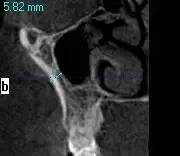

第三圖:上頜竇氣化導(dǎo)致上頜竇過大,上頜竇底骨質(zhì)向紙張一樣薄。只適合做外提升。